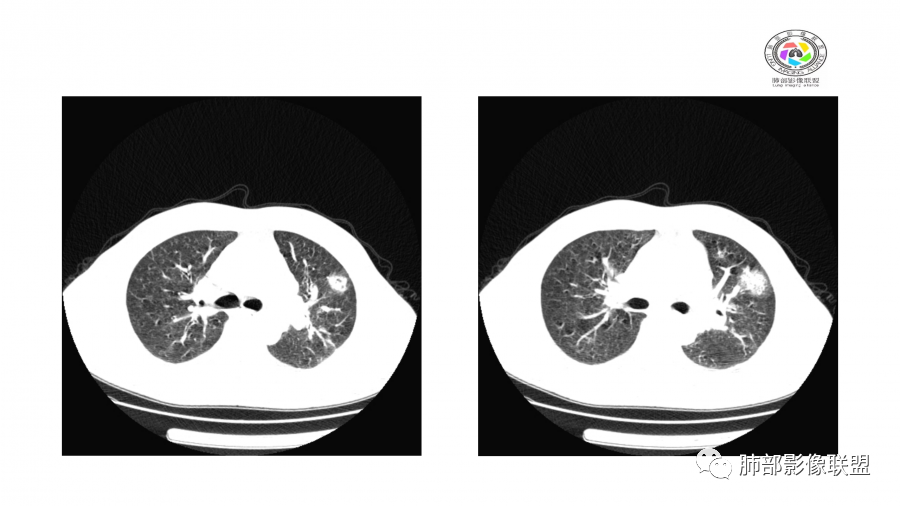

患者,男,49岁,初次以头晕呕吐肾功能异常入院,后期伴双下肢水肿,CT示双肺多发斑片及结节影,部分周围伴晕,部分内部可见支气管穿行,多次复查可见部分病灶略吸收及新发病灶出现,最后一次复查双肺多发磨玻璃样改变,综合考虑血管炎,最后一次伴肺水肿可能

中年男性,高血压,肾功能衰竭,贫血病史,尿潜血阳性。3.8双肺野多发斑片磨玻璃实变影,结节影,边缘模糊,周围有晕征,内见支气管充气征,主要沿支气管血管束分布,部分胸膜下分布,3.12号病灶有吸收好转,4.8号斑片实变影基本吸收,主要沿支气管血管束分布结节影,边缘平直收缩,4.28病灶大部分吸收好转,双肺支气管血管束增粗,有少量结节影。考虑ANCA相关性血管炎可能性大,第一次片子觉得隐球菌不排除,但是后面没有抗真菌治疗就吸收了,觉得隐球菌可能性不大。

影像:双肺散在实变影及毛玻璃影,实性病变周围可见晕征,病灶于肺外围区域优势分布,病变区引流支气管未见增厚,考虑血管相关病变;3月、4月复查CT提示肺内病灶呈游走性,此起彼伏。

胸部CT:双肺多发实性斑片影,散在GGO。实性斑片周围可见晕征、边缘模糊不清,病灶于肺外围区域优势分布。肺门区血管影增粗,支气管套袖,目测肺动脉增粗。3月、4月复查肺内实性斑片病灶呈游走性,此起彼伏。